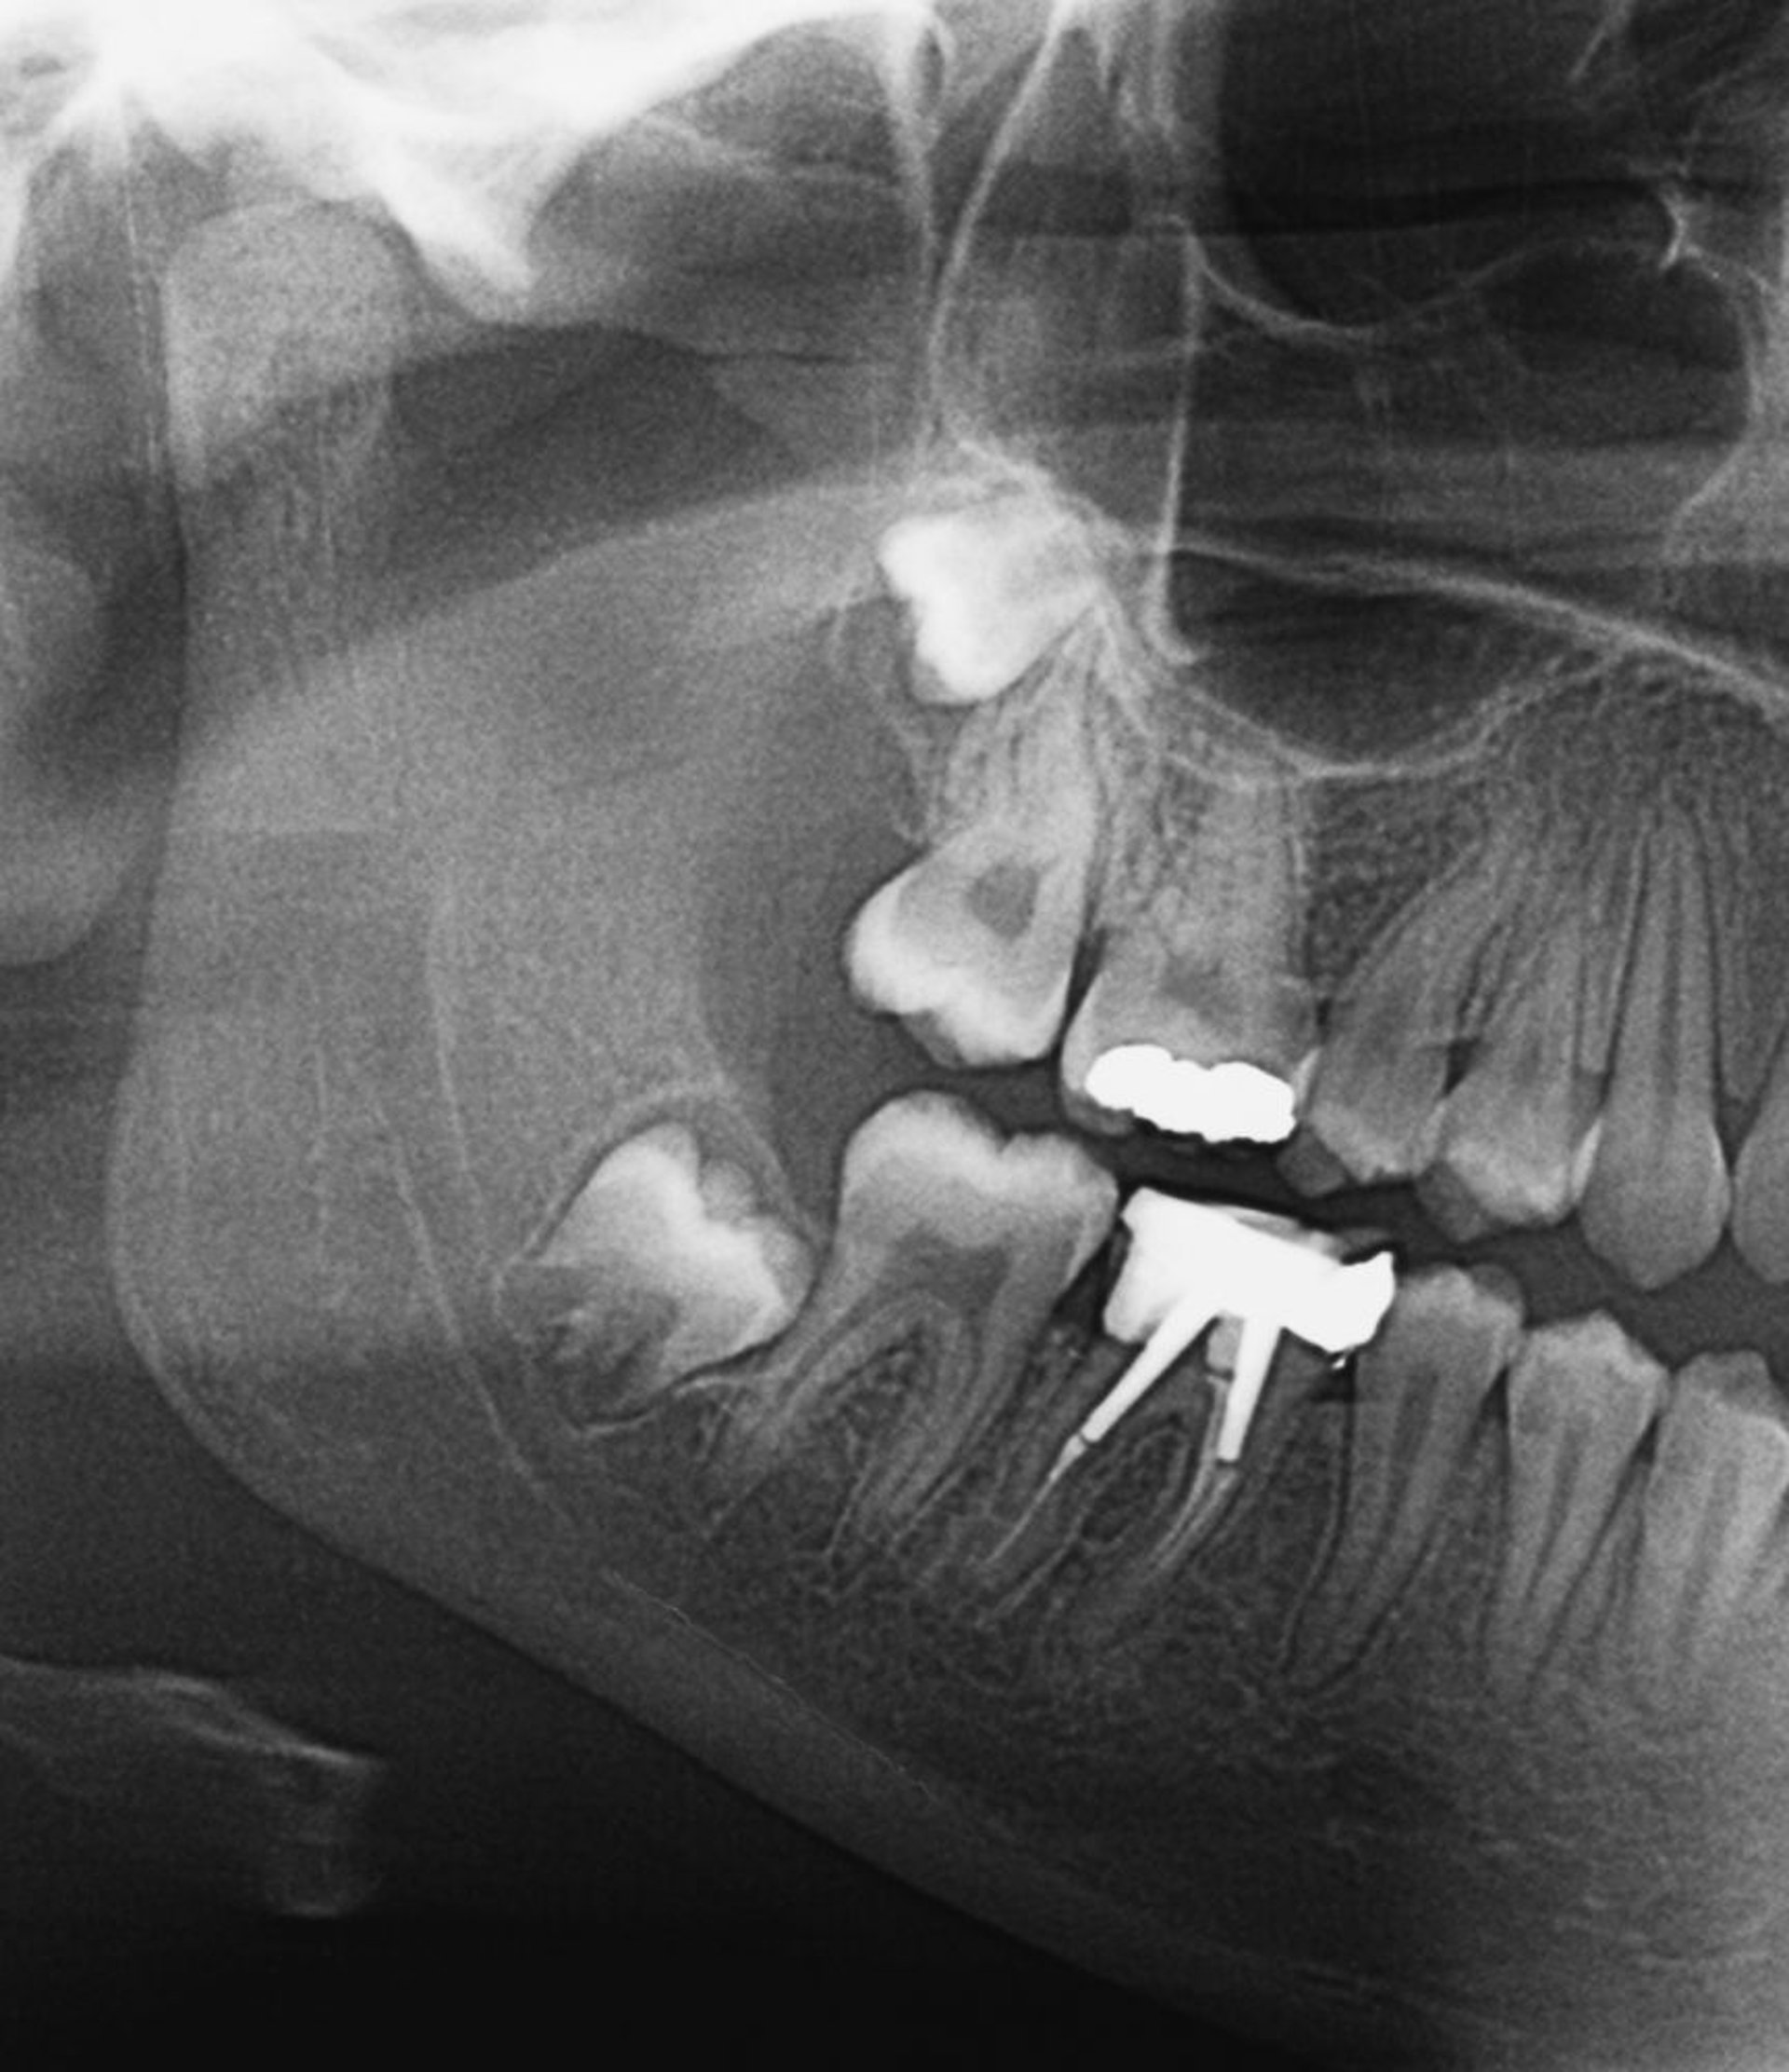

Questa radiografia mostra denti del giudizio ritenuti. Quando crescono i denti del giudizio, o se sono parzialmente ritenuti, può svilupparsi la pericoronite.